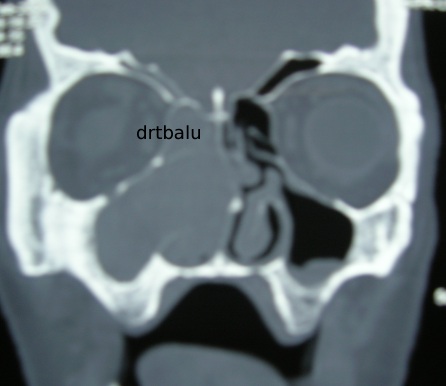

Coronal CT showing nasal polyposis with bone remodelling

One important point that should be borne in mind while evaluating CT images from a patient with nasal polypi is that they never cause bone erosion. If soft tissue mass arising from the nasal mucosa is associated with bone erosion then it is a definite pointer towards the diagnosis of malignancy. Pressure effects of nasal polyp can be evidently seen in imaging. These effects include local bone remodelling causing a scalloping effect. This scalloping effect should not be confused with that of the scalloping of margins produced by the mucocele since it is always associated with enlargement of the sinus cavity. Rarely this bone remodelling may occasionally cause thinning of the bony septa of the ethmoidal sinus. This thinning could be so extreme that it could go even below that of the resolution of the CT scan. This creates a picture of bone erosion which is not a true one.